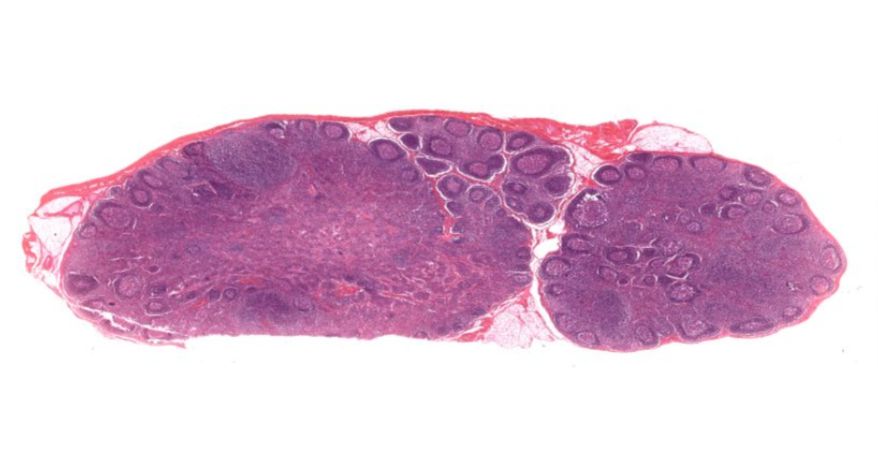

2 淋巴结